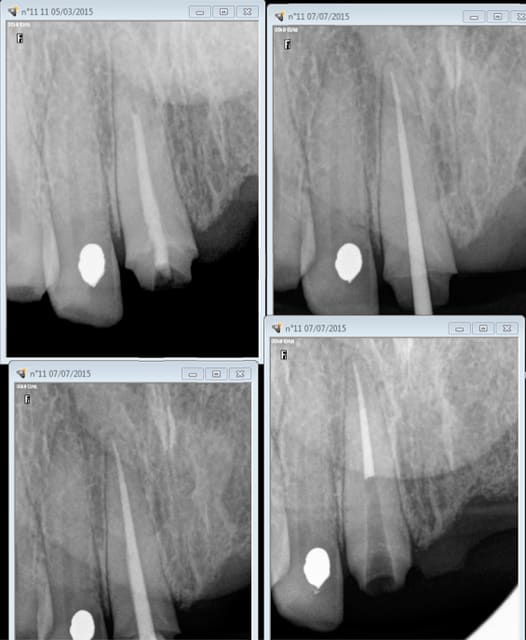

Quand à mon sens de l'ironie j'ai un stock de radios préop, avant RTE, qui prouve que lorsque l'on ne se fait pas payer ce que l'on vaut on finit par valoir ce que l'on se fait payer.